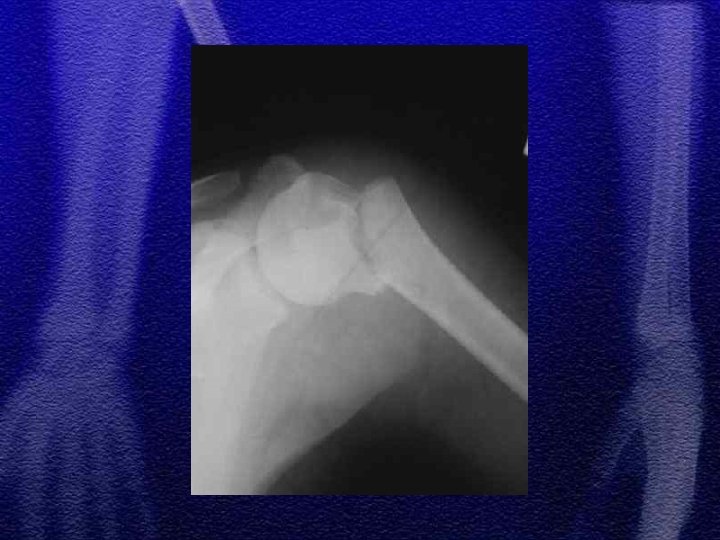

1. złamanie szyjki chirurgicznej (przynasady) 2. zwichnięcie barku występuje u dzieci wyjątkowo rzadko, w starszej grupie wiekowej 3. u dzieci młodszych złuszczenie typ I, u dzieci starszych typ II 4. leczenie: jednoczasowa repozycja zamknięta, wyciąg szkieletowy, leczenie operacyjne rzadko 5. istnieje bardzo duża możliwość przebudowy kości w tej okolicy